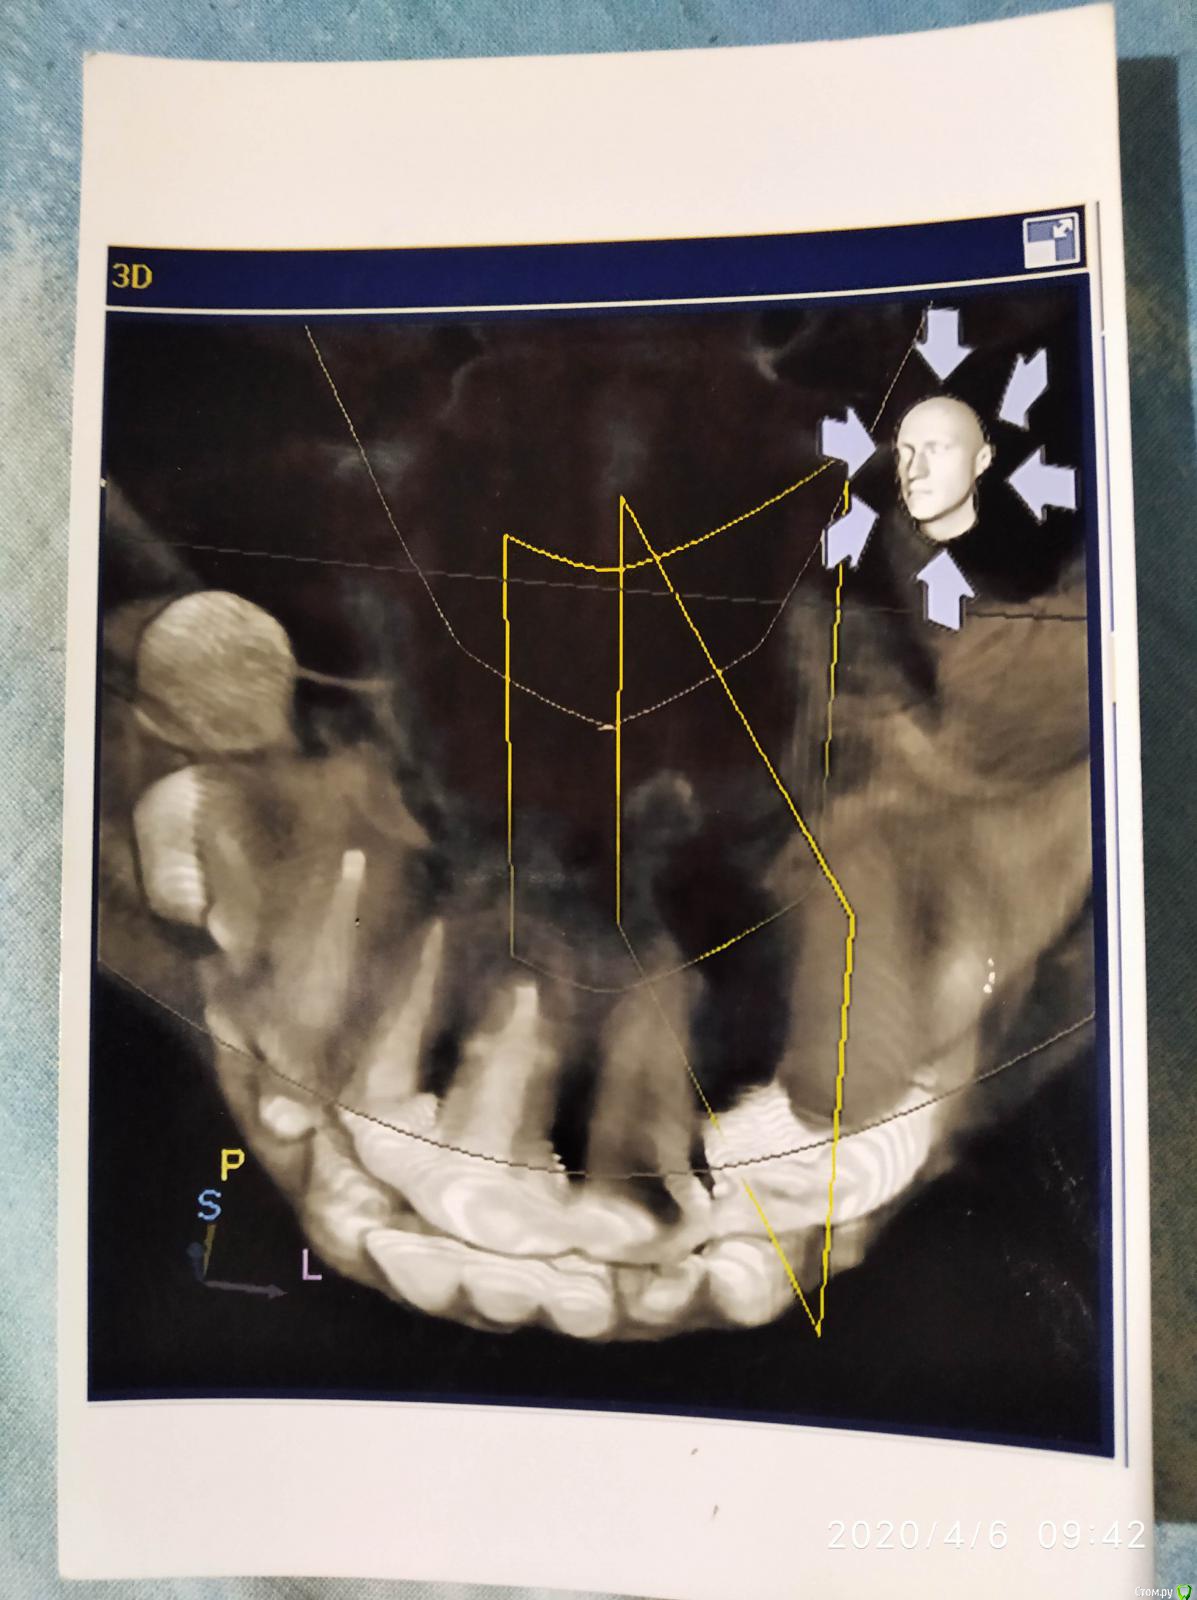

Алексей870 Опубликовано 6 апреля, 2020 Поделиться Опубликовано 6 апреля, 2020 Здравствуйте помогите разобраться образование в верхней челюсти возле резцового канала ..в 2000 году давно мне ставили штифт в верхнюю двоику на снимках этот зуб удален уже и после лечения зуба начало закладывать нос аллергия боли лицевые .сделал КТ челюсти там обнаружилось образование .в 2015 году челюстно лицевом хирург попытался удалить но не долез до него достал только как он сказал вату с челюсти откуда она там взялась...есть мысли что стоматолог что-то мне туда загнал в челюсть .. Ссылка на комментарий

Bier Опубликовано 6 апреля, 2020 Поделиться Опубликовано 6 апреля, 2020 похоже на пломбировочный материал, он высоко, прямо под носом. Но удалить можно Ссылка на комментарий